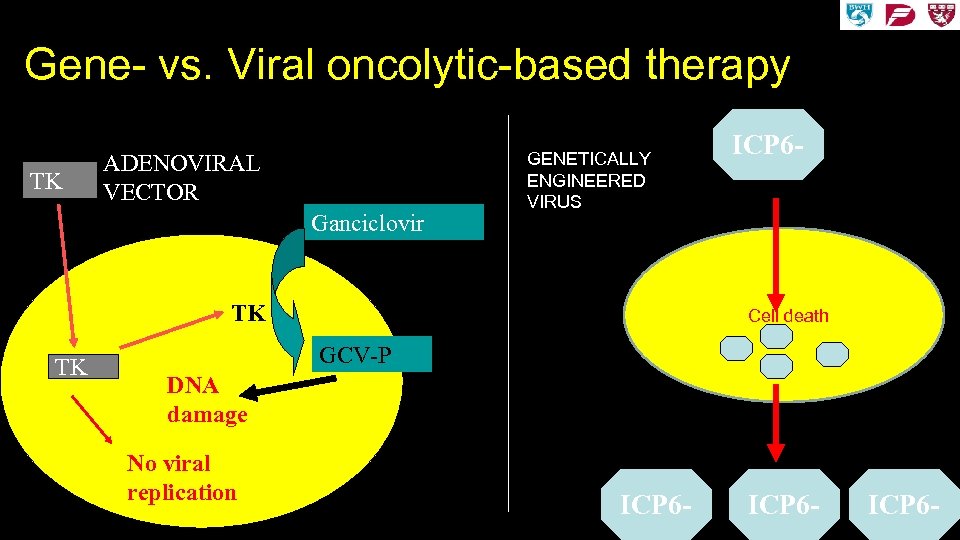

Gene- vs. Viral oncolytic-based therapy TK ADENOVIRAL VECTOR Ganciclovir GENETICALLY ENGINEERED VIRUS TK TK ICP 6 - Cell death GCV-P DNA damage No viral replication ICP 6 -